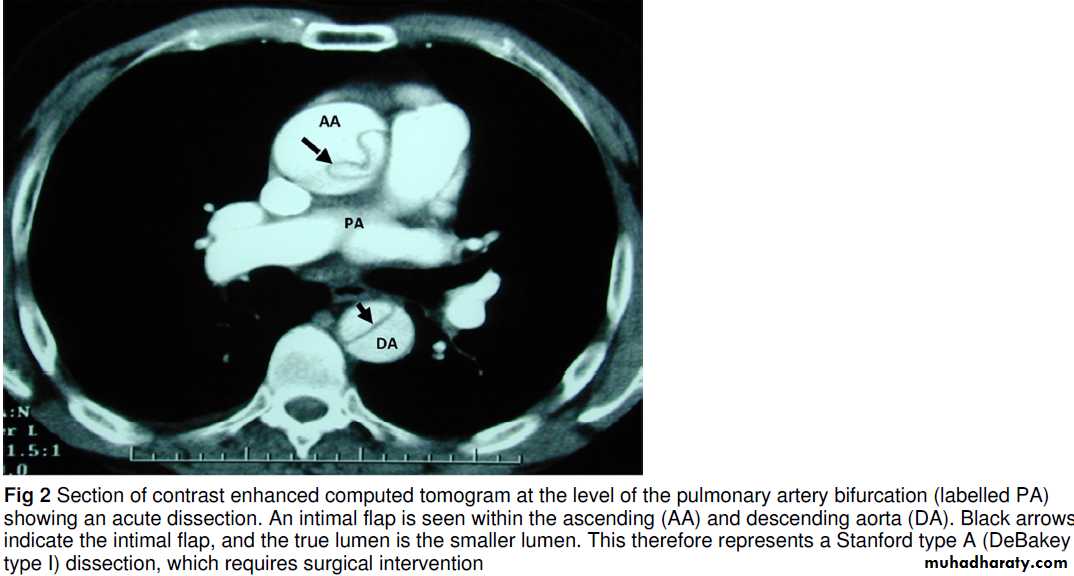

Acute aortic dissection

Acute aortic dissection is caused by an aortic intimal tear with propagation of a false channel in the media. Depending on the site and extent of the tear, it may cause chest, back, or abdominalpain, or collapse caused by rupture or malperfusion (transient or persistent ischaemia of any organ as a result of arterial branch obstruction).

For type A acute aortic dissection, untreated mortality is 1-2% per hour in the first day, with a 90% mortality at 30 days. With surgery, this can be converted to 75-90% survival, and no more than two patients need treatment to gain survival advantage.Rapid recognition and treatment (within hours) may prevent the survival attrition and maximise recovery of reversible malperfusion phenomena (including neurological deficit).

Misdiagnosis as acute coronary syndrome may lead to inappropriate administration of anti-platelets and thrombolysis,complicating surgery. For all cases of acute aortic dissection, delayed diagnosis may delay antihypertensive treatment,allowing propagation and worsening of prognosis.

How is acute aortic dissection diagnosed?

ClinicalA triad of symptoms—characteristic chest pain (usually abrupt and/or severe), a pulse deficit or blood pressure differential, and an abnormal chest radiograph—increases the likelihood of dissection but is present in only a third of patients. A pulse deficit is the unilateral absence or diminution of a pulse compared with contralateral palpation. To detect this, a full peripheral pulse examination is mandatory (radial, brachial,carotid, and femoral pulses). The blood pressure differential is defined as a difference in systolic blood pressure between both arms of >20 mm Hg.

Once clinically suspected, a definitive diagnosis is made with cross sectional imaging (computed tomography of the aorta or magnetic resonance angiography) or transoesophageal echocardiography;

each of these imaging techniques has high diagnostic accuracy.